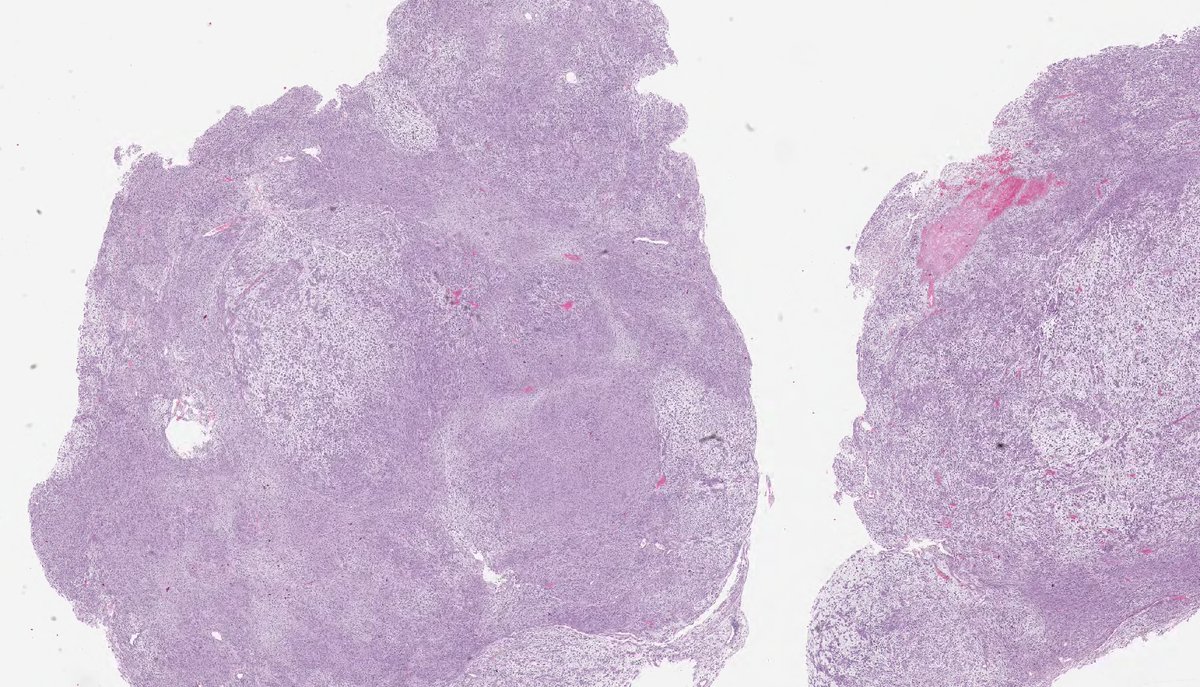

DEDIFFERENTIATED LIPOSARCOMA (with so-called 'low-grade' dedifferentiation). (FISH: + MDM2 amplification.) PMID: 9060596, 9127316.